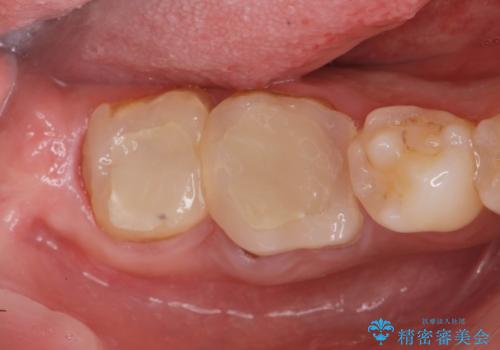

金属のクラウンは薄く加工しても壊れないことがメリットですが、セラミッククラウンを装着するにはスペースが少なすぎ、このまま治療を進めると外れやすく壊れ易いセラミッククラウンの設計となるため、歯周外科を行い狭小なスペースの拡大を行うこととしました。

なんとかギリギリのスペースを確保するこおtができ、無事銀歯を外してセラミック治療を行うことができました。